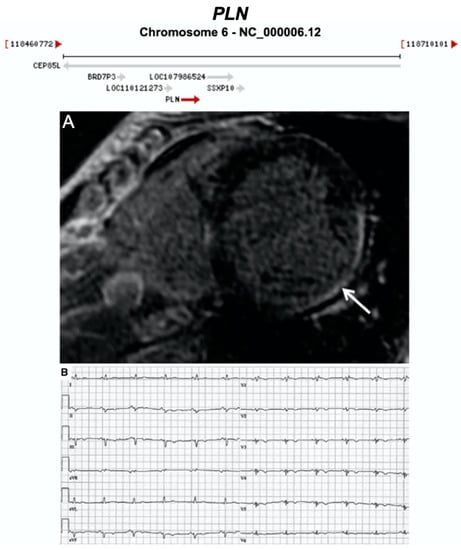

| PLN | Calcium Regulation | 0–12% | AD | LV, BIV | - | 6q22.31; 2 | Founder mutation in Netherlands. High risk of SCD—may consider ICD as primary prevention | Definitive for CMP |

3.2.9. Phospholamban (PLN) (Encoded by PLN)

- Te Rijdt, W.P.; Ten Sande, J.N.; Gorter, T.M.; van der Zwaag, P.A.; van Rijsingen, I.A.; Boekholdt, S.M.; van Tintelen, J.P.; van Haelst, P.L.; Planken, R.N.; de Boer, R.A.; et al. Myocardial fibrosis as an early feature in phospholamban p.Arg14del mutation carriers: Phenotypic insights from cardiovascular magnetic resonance imaging. Eur. Heart J. Cardiovasc. Imaging 2019, 20, 92–100. [Google Scholar] [CrossRef] [PubMed]